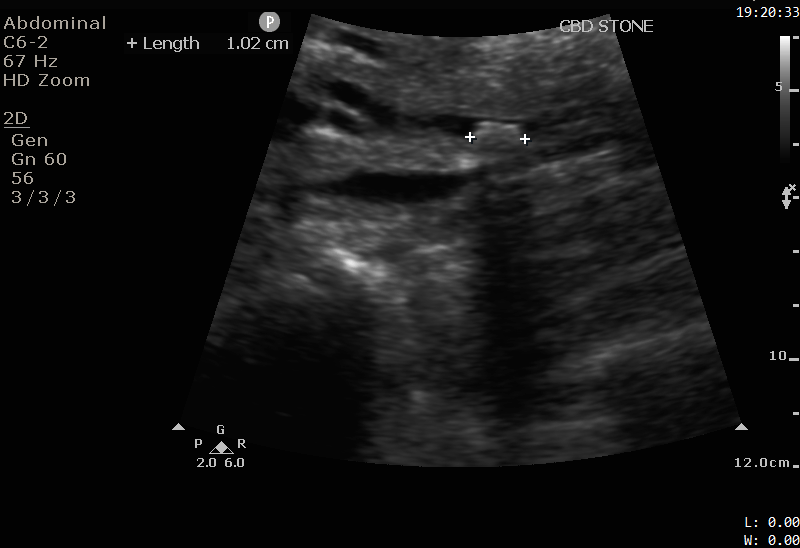

Bedside ultrasound was performed on the ward by the surgical house officer.

The images show a 1cm stone in the distal CBD. Note the hyperechoic (bright white) appearance, with a posterior acoustic shadow, similar to the appearance of gallstones discussed in Case 2. The CBD is not significantly dilated.

Images were shown to the radiologist. MRCP was avoided and the patient proceeded directly to ERCP.